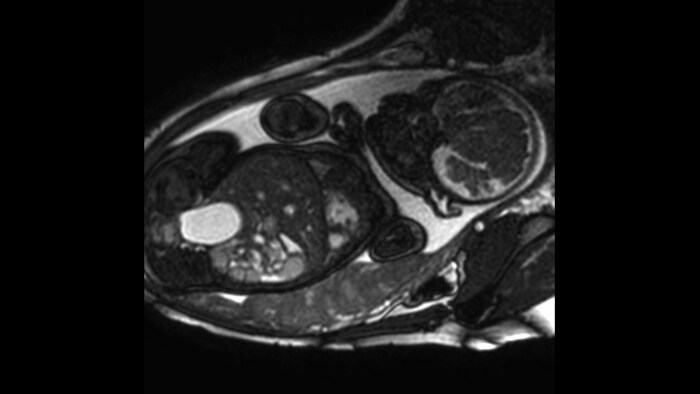

Fetal cardiac imaging examples, gestational age 33-36 weeks.

Short axis view, 1.5T

Short axis view, 3.0T